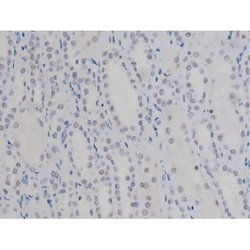

Invitrogen™ Phospho-NPM1 (Thr199) Polyclonal Antibody

Antibody detects endogenous levels of Nucleophosmin only when phosphorylated at Threonine 199.

| Applications | Immunohistochemistry (Paraffin), Western Blot, Immunocytochemistry |